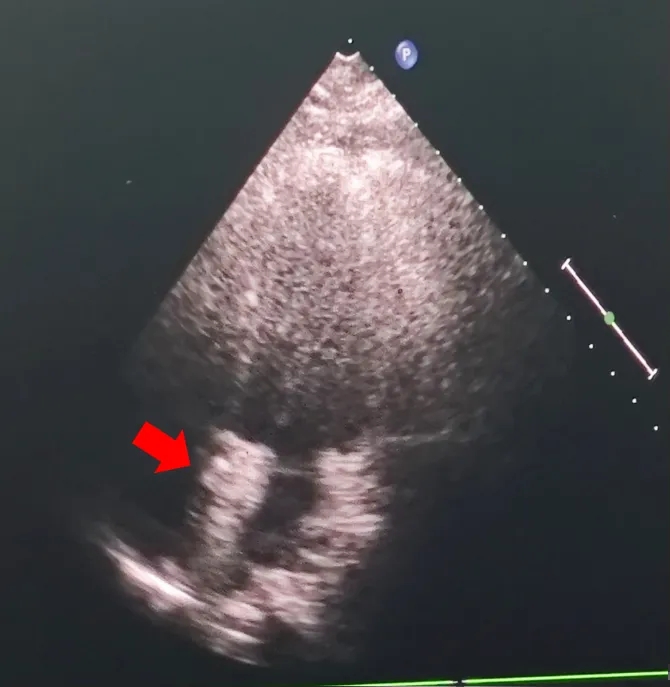

术后超声

超声下可见封堵器左右盘面牢牢贴靠房间隔,且无残余分流,封堵成功

本例为一例37岁女性PFO患者伴偏头痛,房间隔回声中断不明显,略向右心房膨出,宽度18mm,深度5mm,隧道长度约12mm,继发隔厚度约3mm,右房内可见下腔静脉瓣,长度约29mm,摆动明显。右心声学造影示右向左大量分流,属长隧道型、合并下腔静脉瓣的高危PFO病例。植入可降解封堵器后,超声即刻评估显示封堵器定位准确,形态良好,双侧盘片贴合紧密,牢固夹持房间隔组织,未见残余分流。